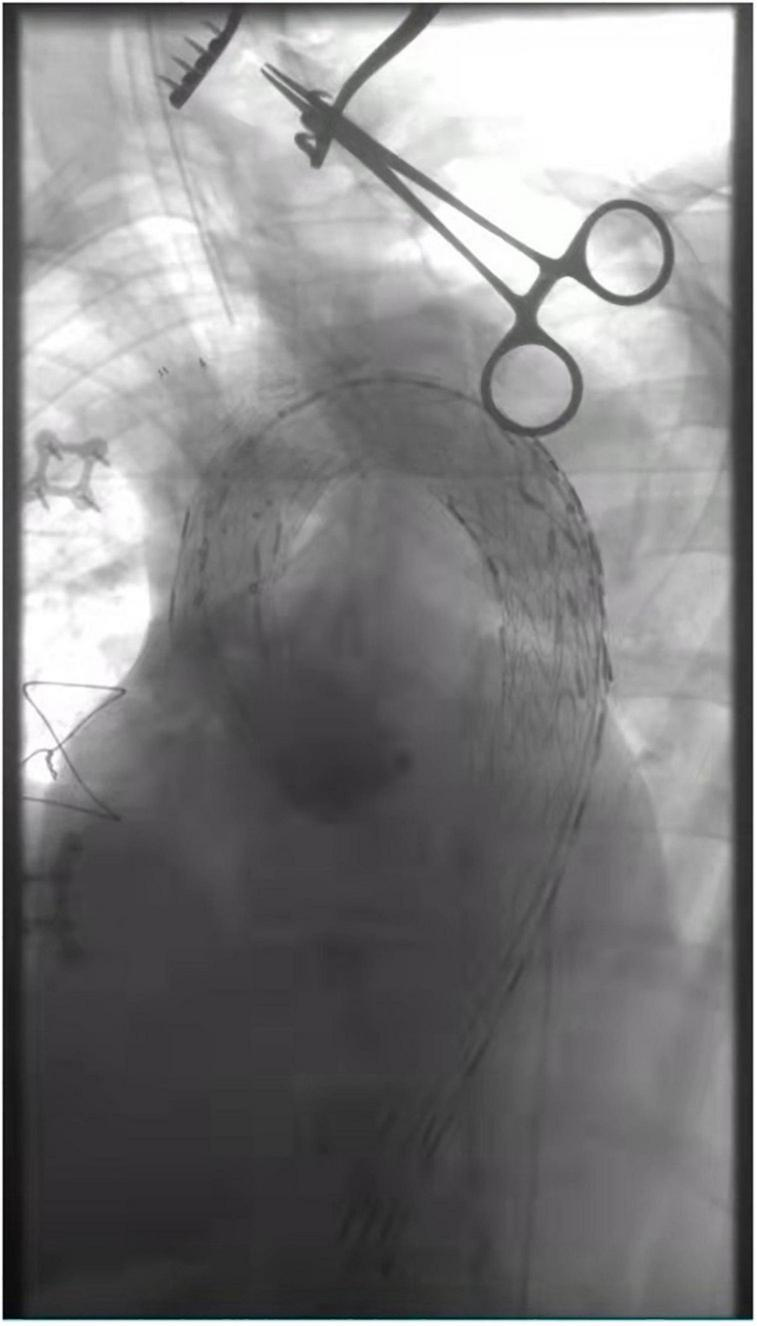

FIGURE 5

The three branches of the aortic arch were well displayed, and the IA, LCA, and LSA were reconstructed with in situ fenestration.